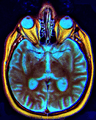

The optic chiasm or optic chiasma (pronunciation: /ɒptɪk kaɪæzəm/; Greek χίασμα, "crossing", from the Greek χιάζω 'to mark with an X', after the Greek letter 'Χ', chi) is the part of the brain where the optic nerves (CN II) partially cross. The optic chiasm is located at the bottom of the brain immediately below the hypothalamus.[1] The optic chiasm is found in all vertebrates, although in cyclostomes (lampreys and hagfishes) it is located within the brain.[2] [3]